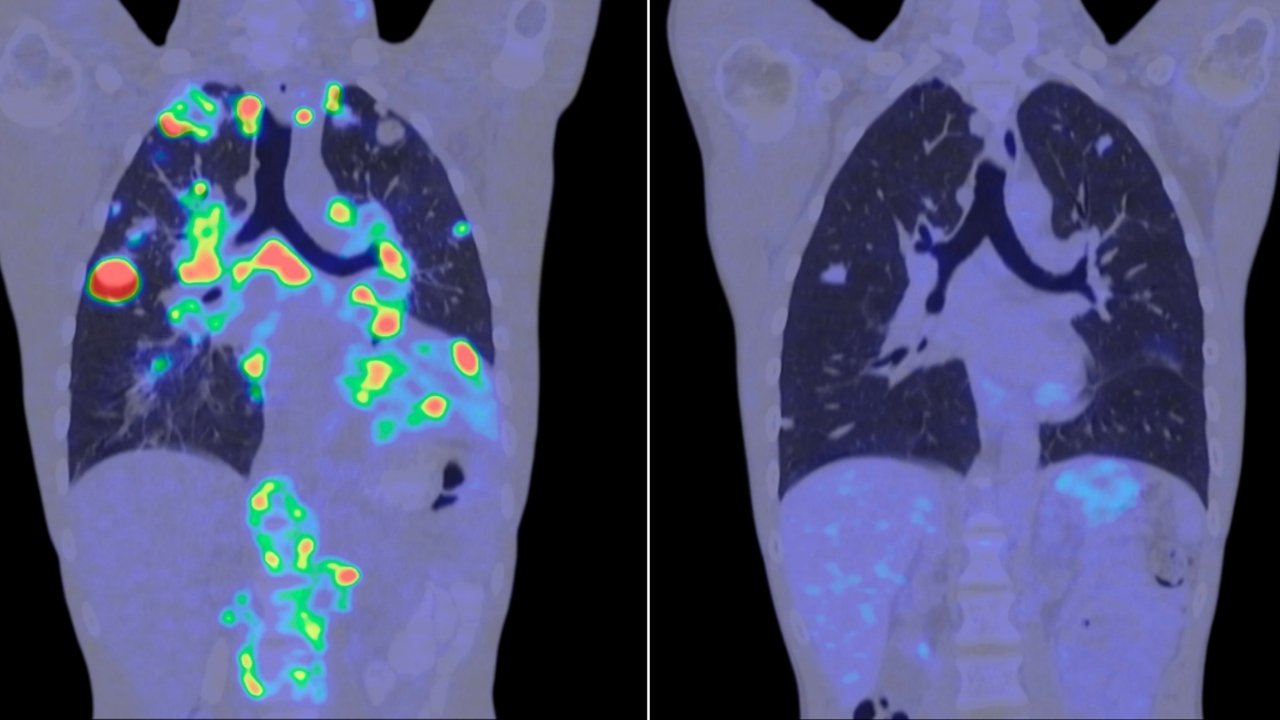

Geleneksel tarama yöntemlerinde insan gözünün veya standart yazılımların kaçırabildiği mikroskobik detaylar, bu yeni protokol sayesinde saniyeler içinde analiz ediliyor. Görüntüleme protokolü, hücrenin çekirdek yapısındaki ve biyokimyasal sinyallerindeki değişimleri takip ederek, tümör henüz kitle haline gelmeden uyarı veriyor.

Yapılan testlerde, modelin meme, akciğer ve prostat gibi yaygın kanser türlerinde %99 başarı oranına ulaştığı gözlemlendi. Uzmanlar, bu teknolojinin yaygınlaşmasıyla birlikte "erken teşhis hayat kurtarır" mottosunun çok daha güçlü bir zemine oturacağını belirtiyor. Özellikle biyopsi gibi invaziv işlemlerden önce bu AI protokolünün kullanılması, teşhis süreçlerini hem hızlandıracak hem de hastalar için daha konforlu hale getirecek.